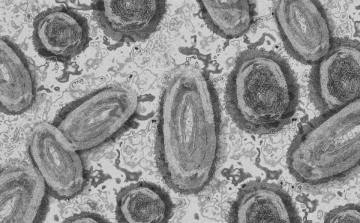

Tovább nőtt a majomhimlő-fertőzöttek száma Magyarországon

Újabb két embernél igazolt majomhimlő-fertőzést a Nemzeti Népegészségügyi Központ (NNK) a 33. héten - augusztus 15-től 21-ig -, ezzel 64-re nőtt a magyarországi esetek száma.

Egy 3 év alatti gyermek fertőződött meg majomhimlővel Belgiumban

Belgiumban egy 3 év alatti gyermek fertőződött meg majomhimlővel - számolt be róla szerdán a Sudinfo hírportál.